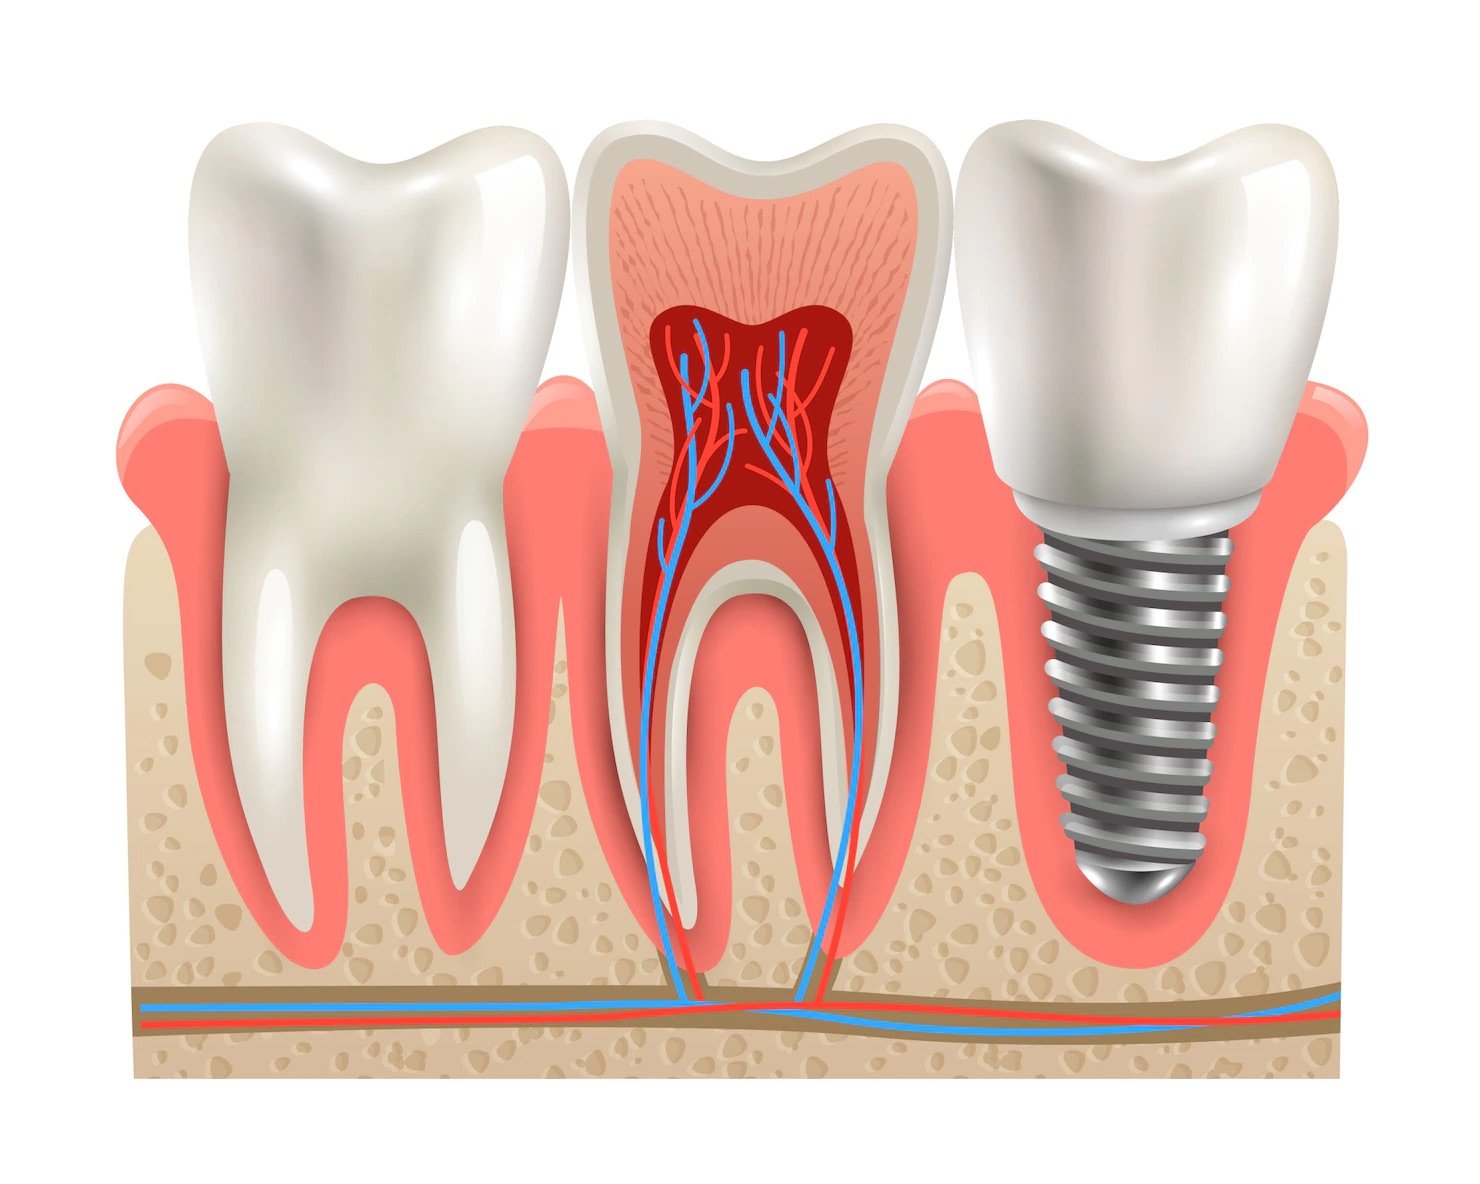

A dental implant is a structure that replaces a missing tooth. With screw-like devices, the dental surgeon inserts an implant into the jawbone, and it acts as an anchor for an artificial tooth, called a crown.

The crown is custom-made to fit the patient’s mouth and match the colour of their teeth. Crowns look, feel, and function like natural teeth.

The most common type of implant is the endosteal implant, which is placed directly into the jawbone. This type of implant is typically made of titanium and is shaped like a small screw.

Endosteal implants are the most commonly used type of implant, as they provide a strong and stable foundation for the replacement tooth or bridge.

A dental implant is a structure that replaces a missing tooth.

With screw-like devices, the dental surgeon inserts an implant into the jawbone, and it acts as an anchor for an artificial tooth, called a crown.

The crown is custom-made to fit the patient’s mouth and match the colour of their teeth. Crowns look, feel, and function like natural teeth.